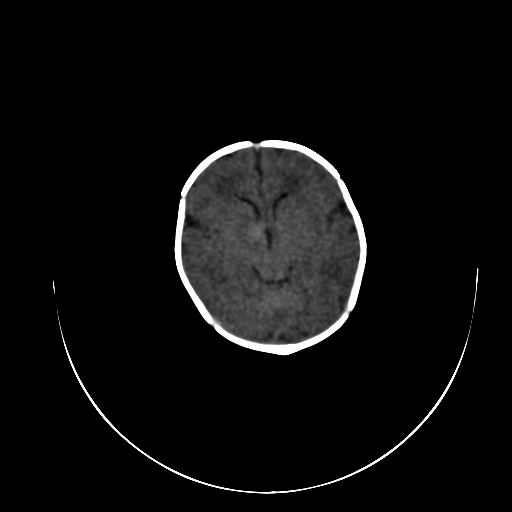

标题: PED0840:女,1.6岁,全身粘膜黄染6天,医生考虑新生儿胆红素 [打印本页]

标题: PED0840:女,1.6岁,全身粘膜黄染6天,医生考虑新生儿胆红素

正常  机器伪影

双侧脑实质多发低密度灶;是图象燥声?烟雾病?         右基底节到顶叶高密度灶,长轴大于宽度,伪影?出血灶??

机器伪影,每层都有,如果是病灶那不成了园柱形的了吗

每层都有且没有改变,应该是机器伪影。

谢谢拉,经过第二次扫描,就没有看见了,

开始我们也怀疑是机器伪影,但又怕是其他的。

不敢下结论。